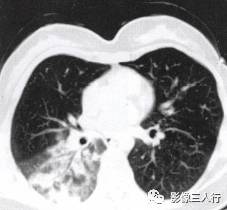

胸部CT图像显示,在含气少的致密肺的背景上见到含气的支气管,表现为两种形态: ①在大片肺实变病灶内的细条状空气密度影;②直径Imm的小泡状空气密度影,连续的几 个层面都能出现(图2、图3)。该征象表明:①近侧气道通畅;②肺泡内的空气经吸收(肺不张)或取代(肺炎、肺癌),或两者综合而消失。通畅含气的支气管在肺泡实变高 密度区内表现为管腔内低密度充气轮廓。 医学百科网 | YxBaike.Com